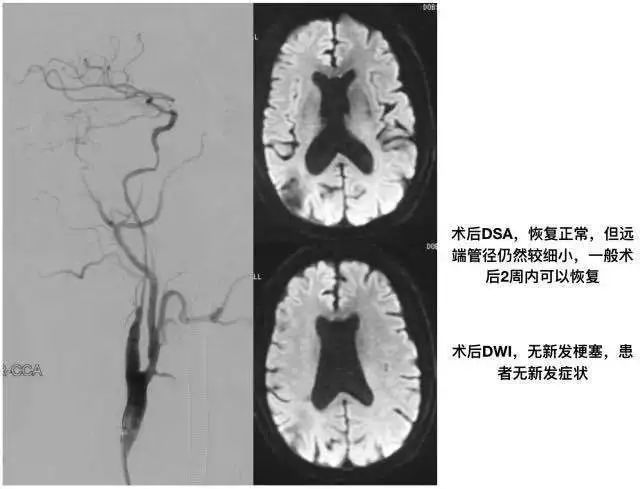

近期做了两个非常类似的CEA手术,都是颈内动脉极重度狭窄,恰逢好友黄亚波教授也提及该疾病,索性将自己的认识简单整理一下,希望对更多的医生有所帮助。

颈动脉重度狭窄斑块内出血导致斑块体积增大,管腔缩窄,表现为假性闭塞,但可能因为及时双抗,所以未出现血栓或栓子脱落,因此,患者虽然反复发作,但梗塞灶始终位于分水岭区域,这种情况下,早期手术是有意义的,再灌注损伤的风险也很低。

同样行CEA,备复合手术

该患者并没有斑块内出血和斑块增大的表现,但斑块远端内膜下和中膜层明显的出血,且呈现不同时期的出血(红色血栓、黑色陈旧血栓、黄染),从而导致最狭窄处并不在斑块处,却是在斑块的远端,类似夹层样的结构,可能因为病史较长,所以有明显的内膜和纤维样增生。对应患者梗塞的部位,与前一例不同,更像是局部血栓脱落导致的栓塞,在数年间,虽给予规范的双抗和单抗治疗,但未予有效手术或介入治疗,所以又出现了低灌注的慢性缺血症状。